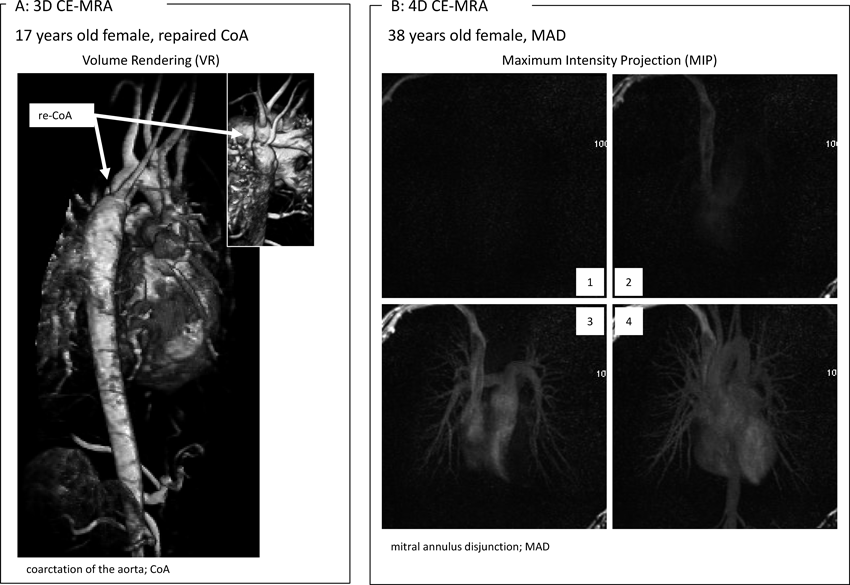

3D CE-MRA(first pass CE-MRA)

Fig. 6 Contrast Enhanced MRA (CE-MRA)

4D CE-MRA(Time resolved CE-MRA)

4D CE-MRAは,3D CE-MRAとkeyhole imagingとを組み合わせることにより,3D CE-MRAを複数の時相で撮影する方法である(Fig. 6B3).keyhole imagingとは,k空間(=MR信号を格納したデータ空間)中心部の信号(=主にコントラストに関係する信号)を高速収集しつつ,k空間辺縁部の信号(=主に鮮鋭度に関係する信号)収集を時々収集し組み合わせることで,造影剤の動きを細かく追跡しつつ,ある程度の空間分解能も保つk空間充填法である3).時間分解能の高い画像が得られるため,time resolved CE-MRAとも表現される3, 28).なお,4D CE-MRAでも3D CE-MRAと同様に体動や呼吸運動によるアーチファクトが生じやすいため,鎮静や息止めでの撮影を考慮する必要がある.